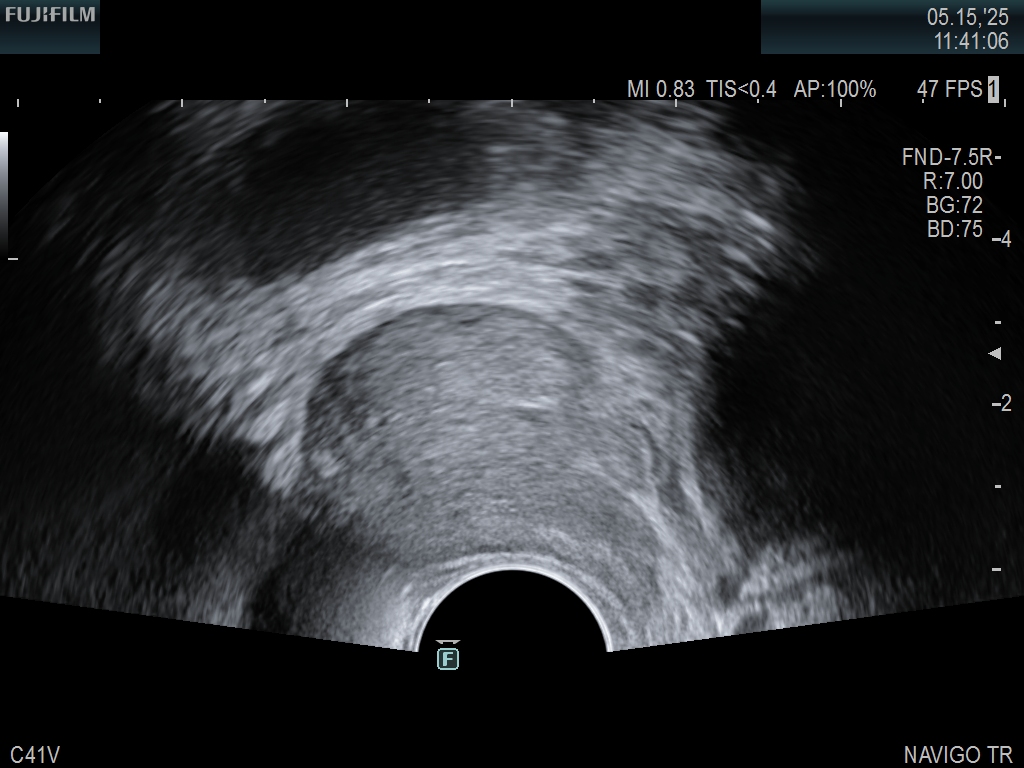

Exclusive 200° field of view end-fire prostate biopsy transducer. Allows visualization of the entire gland from apex to base.